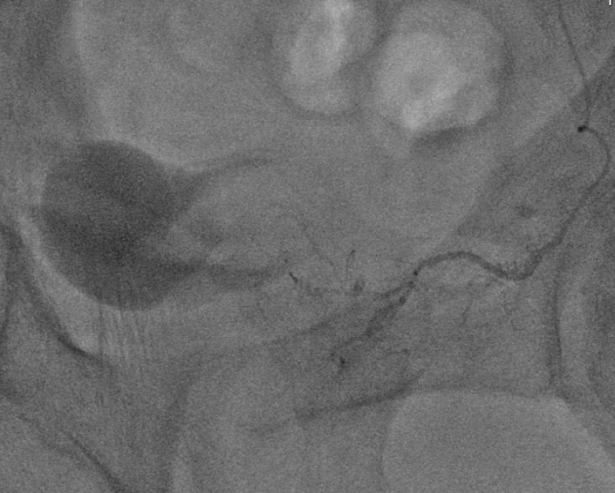

圖一:治療過程

左圖:微導管置入攝護腺動脈,注射顯影劑確認位置正確,確認之後開始進行栓塞治療。

右圖:栓塞前的術中電腦斷層,確認攝護腺的顯影,表示導管正確置入攝護腺動脈。